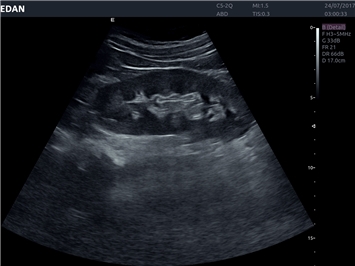

EDAN Acclarix LX4 представляет собой инновационную ультразвуковую систему, построенную на усовершенствованной платформе Acclarix. Сочетание высокого качества визуализации с интеллектуальным рабочим процессом делает эту систему оптимальным выбором для клиник, ценящих эффективность и экономичность.

• Общей визуализации

• Акушерства и гинекологии